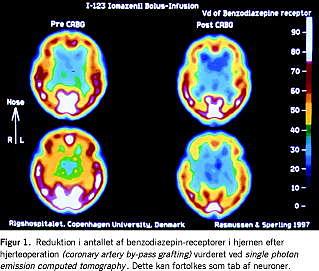

Det er efterhånden godt dokumenteret, at POCD er en hyppigt forekommende tilstand efter kirurgi, men årsagsforholdene er dårligt belyst. Den hyppige forekomst af POCD efter hjertekirurgi er muligvis relateret til peroperativ cerebral embolisering, cerebral hypoperfusion, hæmodilution eller en systemisk inflammatorisk reaktion. I nogle undersøgelser med brug af avanceret billeddiagnostik er der fundet strukturelle ændringer i hjernen forbindelse med hjertekirurgi, blandt andet et reduceret antal neuroner (Figur 1 ). En beskadigelse af hjernecellerne har været foreslået som en årsag til POCD, idet dyreeksperimentelle undersøgelser har fundet en neurotoksisk effekt af anæstesimidler, men også hormoner eller inflammatoriske mediatorer kan påvirke den kognitive funktion. Hospitalsmiljøet og mekanismer i forbindelse med sygdom og indlæggelse kunne også have betydning, f.eks. relateret til forstyrrelser i døgnrytme, søvnmønster samt fødeindtagelse, og søvnforstyrrelser synes at være associeret til POCD efter større kirurgi.